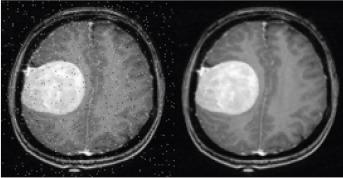

MRI Brain Tumour Segmentation Using Hybrid Clustering and Classification by Back Propagation Algorithm.

Generally the segmentation refers, the partitioning of an image into smaller regions to identify or locate the region of abnormality. Even though image segmentation is the challenging task in medical applications, due to contrary image, local observations of an image, noise image, non uniform texture of the images and so on. Many techniques are available for image segmentation, but still it requires to introduce an efficient, fast medical image segmentation methods. This research article introduces an efficient image segmentation method based on K means clustering integrated with a spatial Fuzzy C means clustering algorithms. The suggested technique combines the advantages of the two methods. K means segmentation requires minimum computation time, but spatial Fuzzy C means provides high accuracy for image segmentation. The performance of the proposed method is evaluated in terms of accuracy, PSNR and processing time. It also provides good implementation results for MRI brain image segmentation with high accuracy and minimal execution time. After completing the segmentation the of abnormal part of the input MRI brain image, it is compulsory to classify the image is normal or abnormal. There are many classifiers like a self organizing map, Back propagation algorithm, support vector machine etc., The algorithm helps to classify the abnormalities like benign or malignant brain tumour in case of MRI brain image. The abnormality is detected based on the extracted features from an input image. Discrete wavelet transform helps to find the hidden information from the MRI brain image. The extracted features are trained by Back Propagation Algorithm to classify the abnormalities of MRI brain image.